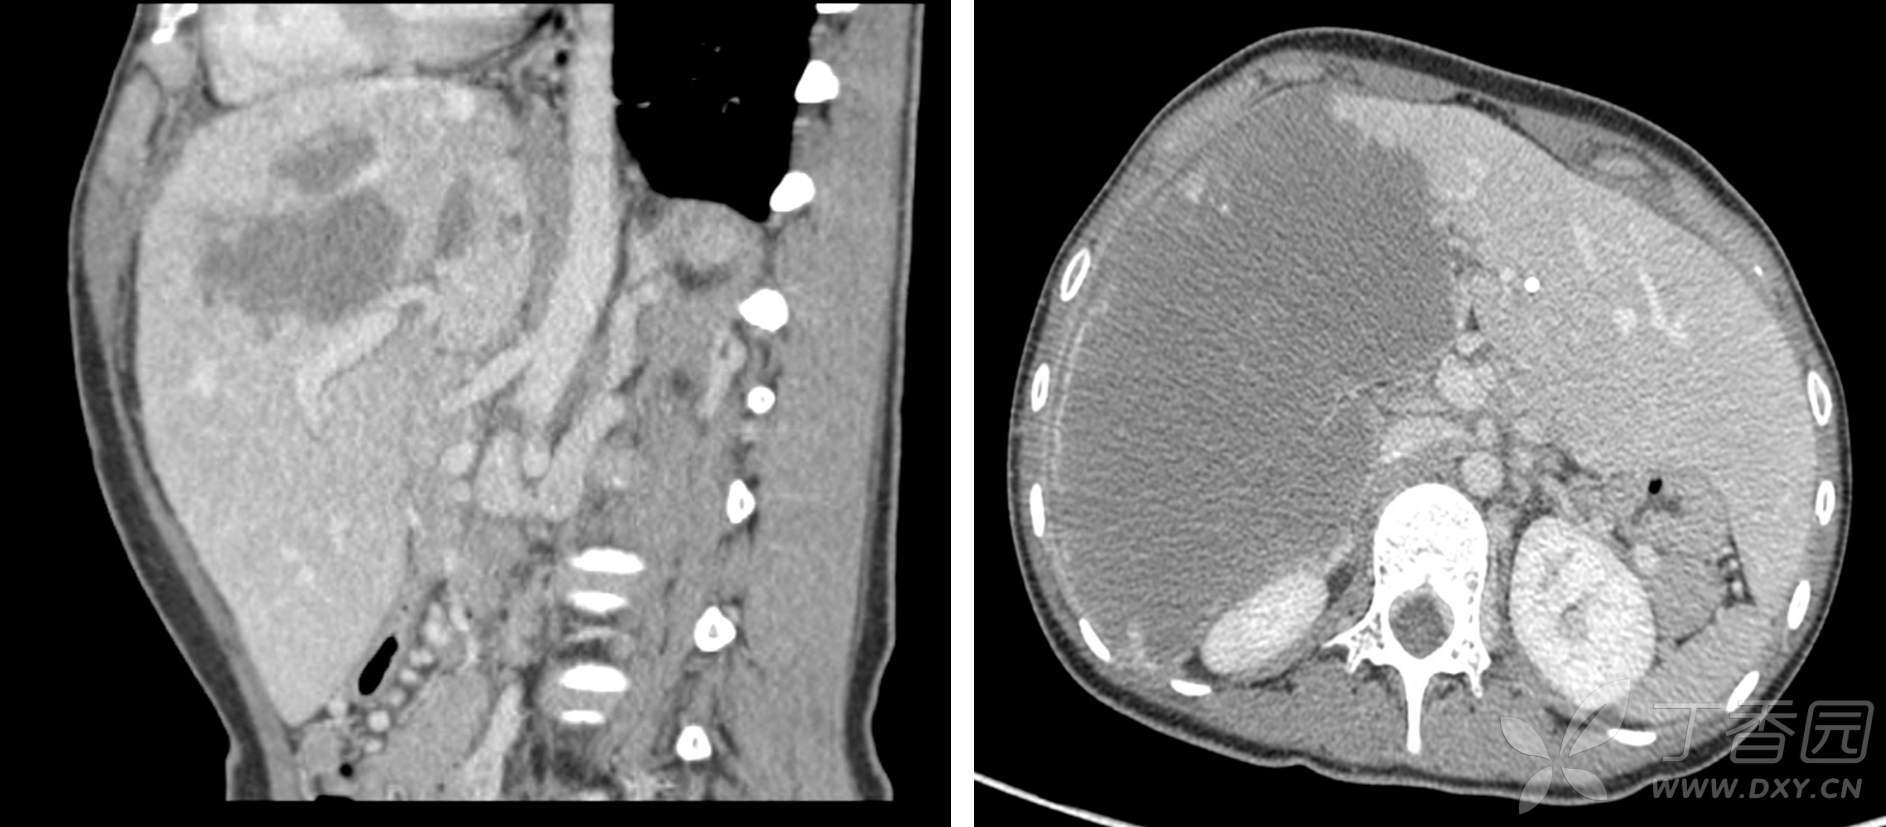

入院后予PTBD减黄,肝功能恢复正常。腹部增强CT提示:病变呈地图样表现,符合肝泡型包虫病特征;病灶主要位于肝脏右三叶,大小约12.1cm*15.4cm*19.2cm;病灶侵犯肝右动脉,门静脉右支全程及左支矢状部受侵,肝右静脉及肝中静脉全程受侵,肝左静脉-腔静脉汇合区受侵,肝中静脉与肝左静脉侧支循环开放,肝后及肝下下腔静脉严重侵犯闭塞,腹膜后侧支循环充分开放,肝左外叶代偿性增生。如图1:

图1 腹部CT血管成像:病灶位于肝脏右三叶,肝左外叶代偿性增生;肝动脉右支受侵,门静脉右支全程及左支矢状部受侵;肝右静脉及肝中静脉全程受侵,肝左静脉-腔静脉汇合区受侵,V2-V3存在侧支循环(蓝色箭头);肝后及肝下下腔静脉严重侵犯闭塞,腹膜后侧支循环充分开放(红色箭头)。

ICG-R15min 6.7%,肝功能Child A级,计算标准肝体积1076ml,左外叶体积1280ml,占患者标准肝体积的121%,剩余肝脏倒是够用的,那就剩一个关键问题,流入流出道完整性能否保证。

流出道:肝后下腔静脉全程受侵闭塞,纵向长度约9.5cm,好在腹膜后奇静脉及半奇静脉已代偿性扩张,因此术中可酌情仅行门腔分流,可不重建肝后下腔静脉。肝右、肝中静脉都已经没了,就连左肝静脉汇入下腔部也受侵,这使得在体切除几无可能,离体切除或许还有点希望。